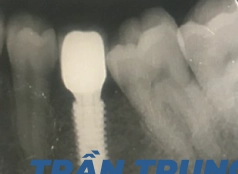

• Bác sĩ chỉ định:Cấy ghép 2 trụ Implant

• Implant sử dụng:Implant Dio Hàn Quốc

• Răng sứ sử dụng:Răng sứ Titan Mỹ

Bác sĩ Phong cũng là người trực tiếp cấy ghép Implant và phục hình sứ cho anh Trung Tín. Toàn bộ quá trình điều trị diễn ra chuẩn xác, nhanh chóng và không có bất kỳ biến chứng nào xảy ra.

Giờ đây, anh Tín đã được khôi phục lại những chiếc răng chắc khỏe, ăn uống thoải mái và không còn phải lo lắng về tình trạng tiêu xương hàm